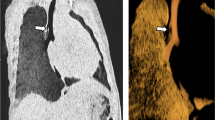

Although bronchoscopy is considered the gold standard to reach diagnosis, imaging shows similar or higher sensitivity compared to bronchoscopy [75]. End-inspiratory and end/forced -expiratory CT imaging is the most used technique to diagnose TBM , and a 50% expiratory reduction in the cross-sectional luminal area is the most often cited criteria for diagnosis of TBM in children [4]. However, this threshold might be too low, as studies in healthy adult subjects have shown that a higher threshold of 70% may be more appropriate to make the diagnosis of TBM [76]. Both bronchoscopy and CT have disadvantages when used in the pediatric population. Bronchoscopy is an invasive procedure that requires anesthesia and CT exposes children to ionizing radiation. In contrast, MR imaging can be performed in free-breathing conditions in infants with no need for anesthesia, or in older children during forced expiration to elicit better the point of airway collapse [18]. Static and dynamic MR imaging are able to demonstrate airway collapse with the same accuracy of CT without the need for ionizing radiation [19] (Fig. 2.24).

Tracheomalacia in a 17-year-old boy with history of tracheoesophageal fistula. (a) Axial nonenhanced proton density-weighted 3D SPGR MR image obtained at end inspiration shows a normal caliber trachea. (b) Axial nonenhanced proton density-weighted 3D SPGR MR image obtained at end expiration shows 75% collapse of the trachea (arrow) and air trapping (asterisk) in the left lower lobe

Fibrosing mediastinitis in a 4-year-old boy who presented with progressively worsening shortness of breath and chest pain. (a) Axial enhanced soft tissue window setting CT image shows excessive soft tissue in the mediastinum and around the large airways with compression of the left main bronchus (arrow). (b) Axial nonenhanced T2-weighted PROPELLER MR image also shows the excessive soft tissue in the mediastinum and around the large airways with compression of the left main bronchus (arrow)